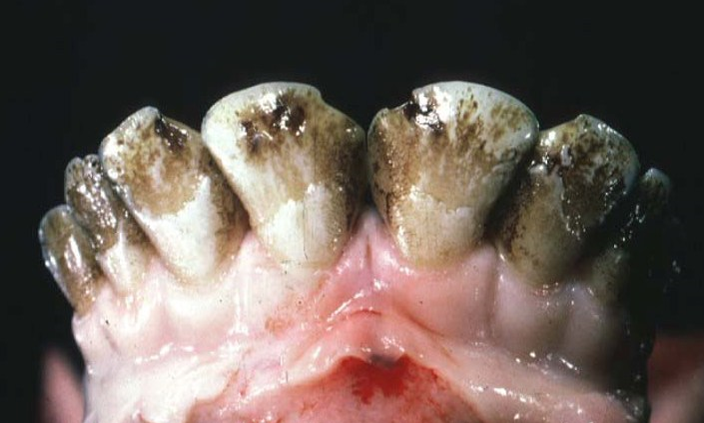

4

Q

What lesion is shown here?

A

enamel hypoplasia